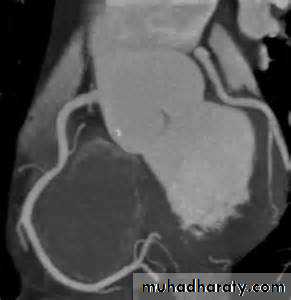

Endoscope -like ultrasound probe which is passed into the oesophagus under light sedation and positioned behind the LA. This produces high-resolution images.Computed Tomographic Imaging :

Useful for imaging the cardiac chambers, great vessels , pericardium, and mediastinal structures and masses

And recently even the coronaries (CT coronary angiography).